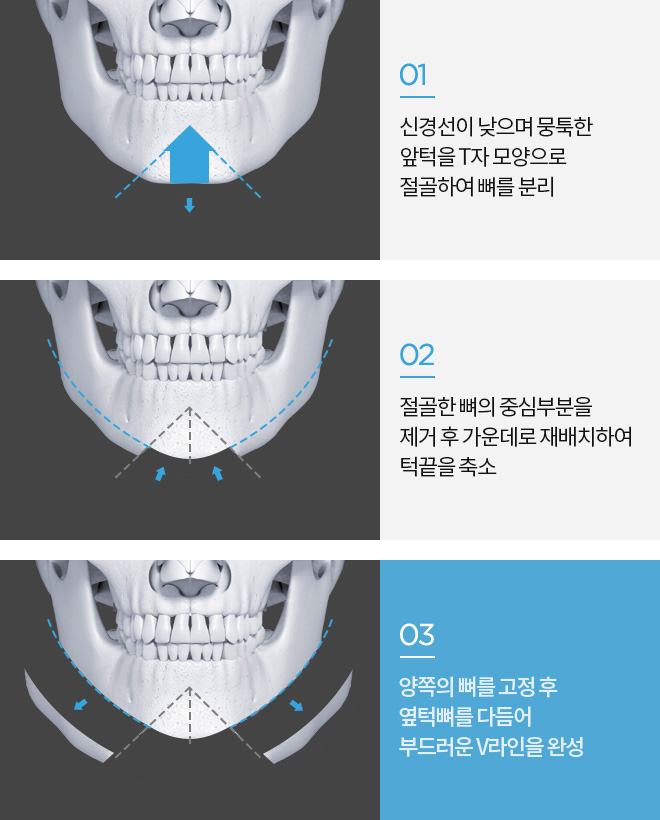

앞턱 절골 수술방법

V 절골법

자연스럽게 턱끝 개선

입안 절개를 통해서 흉터걱정이 없기에 매끈하고 자연스러운 턱끝 모양

개인별 차별화된 수술방법

주걱턱, 왜소턱 등 개인별 턱 모양에 맞춰 차별화된 수술방법으로 균형잡인 턱라인 완성